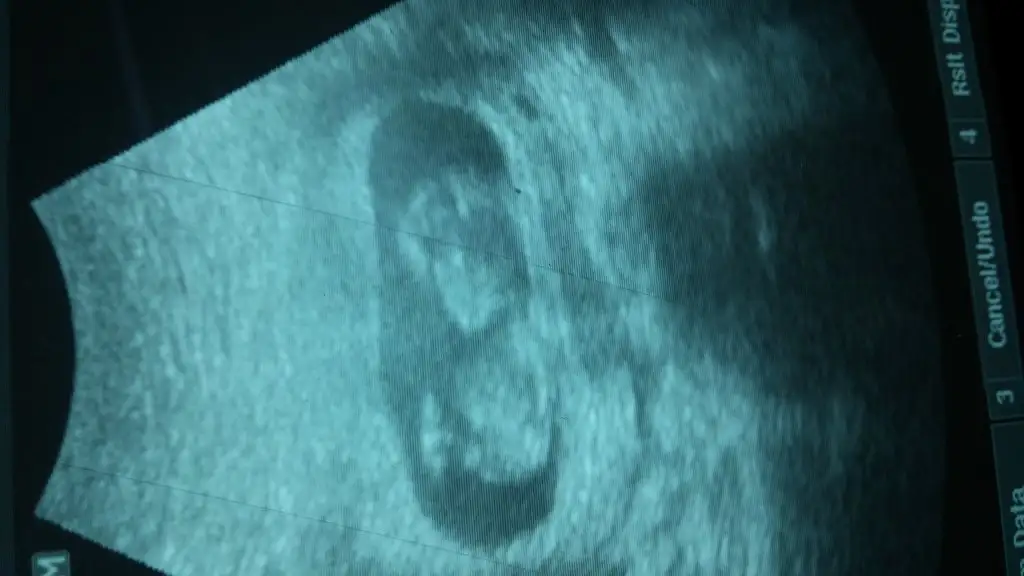

12+3 günlük teyzeleri,cinsiyet tahmini bizede yaparmısınız???Eki Görüntüle 1545346

12 haftalık canım, benımkınde ufak i cıkınrı var bıde parlayan bı taraf bar hangısı nub anlayamadımÇok anlamıyorum ama yinede incelediğim örnekler doğrultusunda kız gibi geldi hayırlısı olsun inşallah sizin kaç haftalıktı ..

Erkek diyorum:)bize de bakar mısın teyzesi

Buna karar veremedim ama sansimi kizdan yana kullaniyorum:)13+4üm hanımlar bugün çekildi banada yorum yapabilir misiniz?